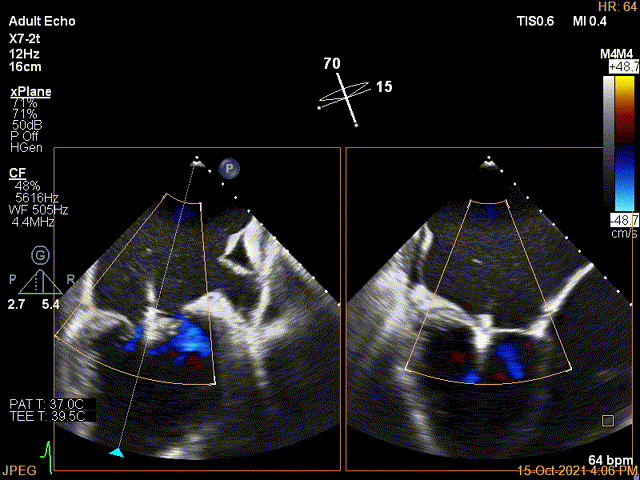

Color第二个夹子内侧残余小束分流,宽2.3mm

第二个夹子放置后二尖瓣口平均跨瓣压差:4mmHg

肺静脉血流频谱恢复正向